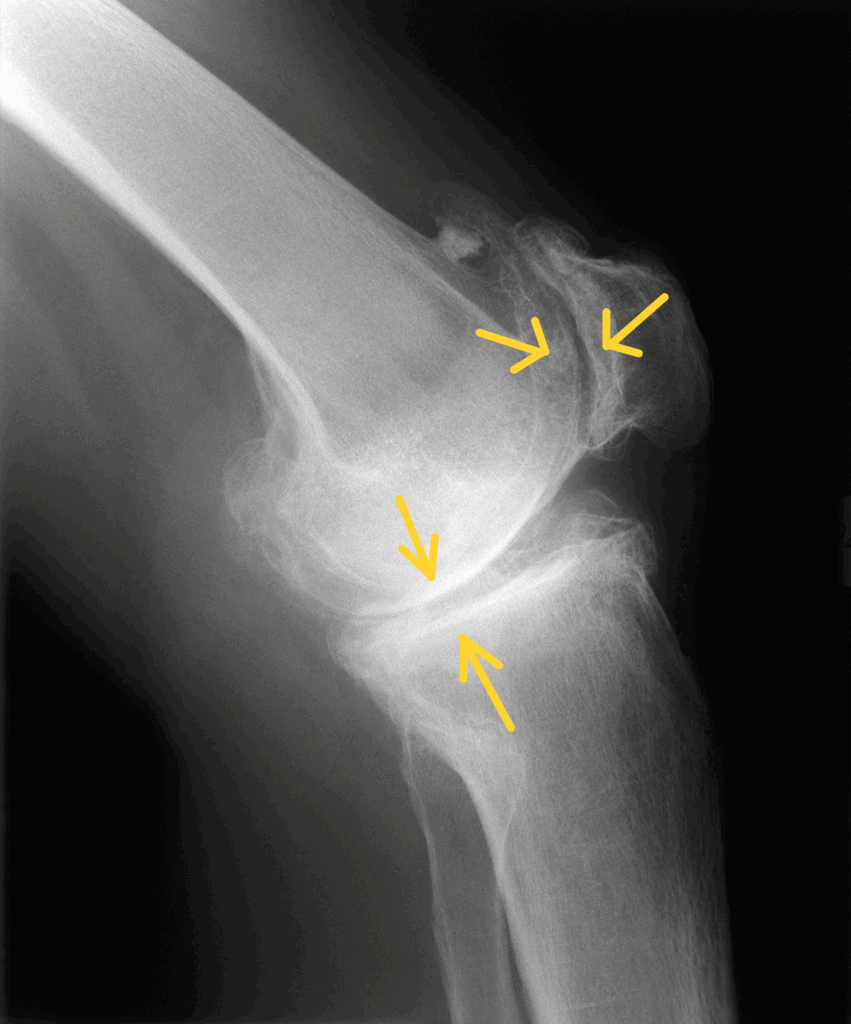

Pangonarthrose: Bei dieser schwerwiegendsten Form sind alle Gelenkkompartimente vom Verschleiß betroffen. Die Symptome sind entsprechend ausgeprägter und die Behandlung komplexer.

Röntgenbild einer schwerwiegenden Arthrose im Kniegelenk mit nahezu aufgebrauchten Gelenkspalt innen- und außenseitig (Pangonarthrose)

| Grad 3 | Deutliche Arthrose | Tiefe Knorpelrisse bis zum Knochen | Starke Schmerzen, Bewegungseinschränkung | Starke Gelenkspaltverschmälerung, Sklerosierung |

| Grad 4 | Schwere Arthrose | Vollständiger Knorpelverlust | Ruhe- und Nachtschmerz, starke Funktionseinschränkung | “Knochen auf Knochen”, ausgeprägte Deformierung |